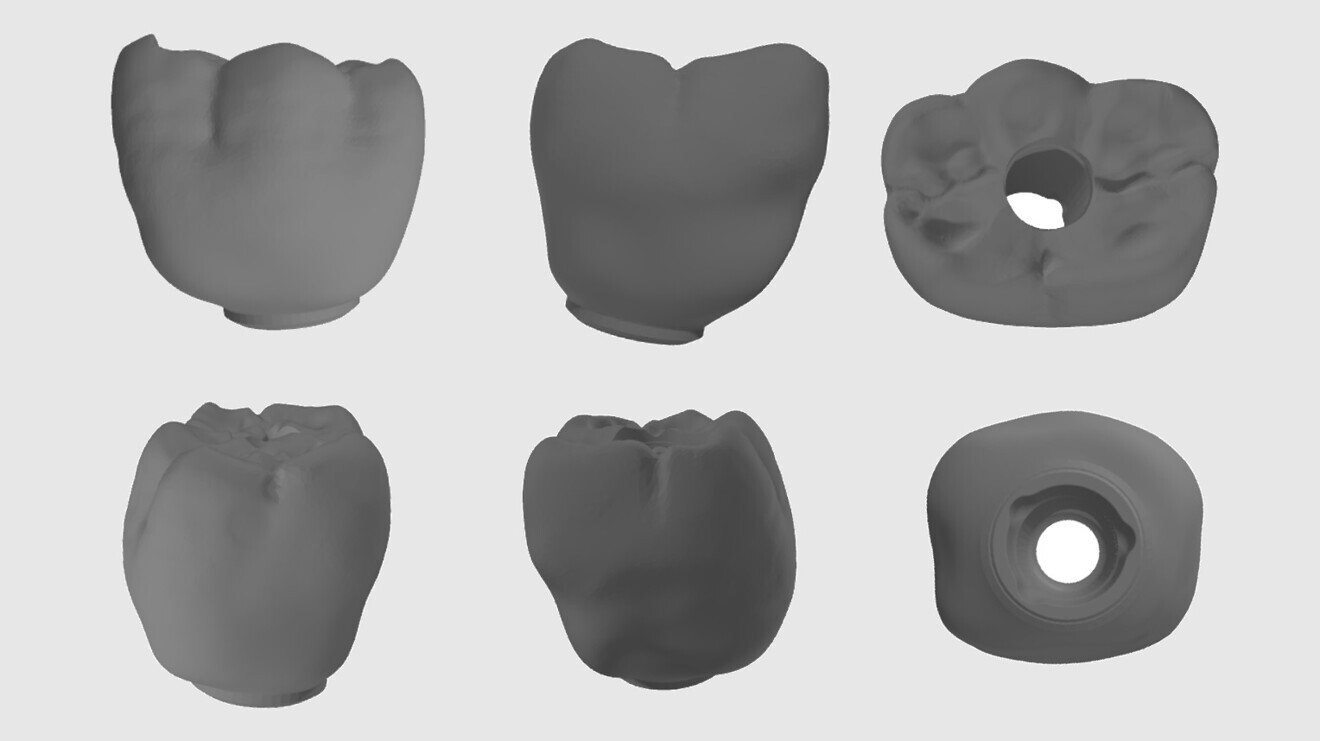

The crown was designed using digital prosthetic libraries (IPD Dental Group) to ensure compatibility with both the Oxy Implant PSK implant system (Biomec) and the selected titanium base (Ti-base). The emergence profile, occlusal morphology and screw access hole were designed to fit precisely on the Ti-base, assuming strict adherence to guided placement (Fig. 4).

Fig. 4: 3D CAD in STL format.

CAD of the crown was performed using the IPD digital library, which offers extensive compatibility with various implant systems and Ti-base geometries. The crown was designed to sit on a Ti-base compatible with the Oxy Implant PSK system and with a screw access hole aligned and sized for retrievability. The emergence profile and occlusal morphology were designed with special attention to the spatial tolerance of the Ti-base interface and insertion axis to ensure passive fit of the prefabricated restoration.